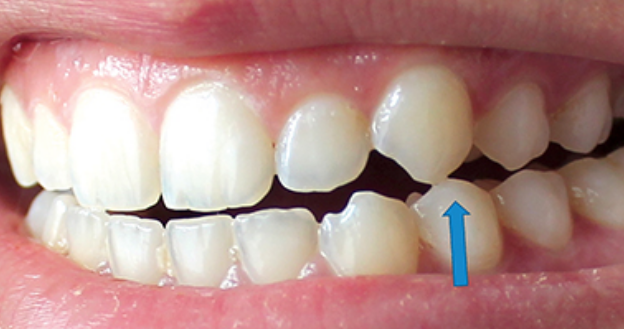

큰어금니와 작은어금니의 갈라진 치아 모습에는 차이가 있는데, 큰어금니의 갈라진 치아는 대부분 “기능적 팁” 쪽, 즉 치아에서 더 큰 스트레스를 받는 부분에서 발생합니다. (아래 포스팅 참조) https://blog.naver.com/sunnyflow/222654941394 Q-ray 촬영으로 어금니 크랙(균열)을 미리 확인하고 대비할 수 있습니다. 닥터&치주과의사 최순호 입니다 오늘은 어금니 중문으로 가는데… blog.naver.com 물론 기능교두의 기능교두는 작은 어금니에도 크랙이 생기는 경우가 많은데, 치아가 부러지는 원인. 음식을 씹을 때 위아래로 씹지 말고 나란히 씹는다. 이것을 치과 용어로 “Lateral Guidance”라고 하는데 위 사진에서 색종이(교합용지)를 찍으면 치아에 가해지는 힘이 화살표 방향으로 퍼지는 것을 볼 수 있습니다. 다시 케이스로 돌아가서 왼쪽 위 어금니가 이전에 근관치료와 크라운 치료를 받았고 씹을 때 불편하다고 하셨습니다. X-레이를 보면 치근/크라운 치료를 받은 어금니 주변에 어두운 그림자가 보일 것입니다. 뼈가 녹으면서 “J자 모양”이 되고 X-레이에서 보이는 이러한 방사선학적 변화는 종종 치아의 깊은 층에 균열이 있음을 나타냅니다(크라운 뿌리 균열, 뿌리 균열 = 치근. 갈라진 치아). 측방 구강 내부에서 송곳니가 곧게 연마되는 것과 같이 측면 안내 중에 치아가 강한 측면 힘을 받는 것으로 추론할 수 있습니다. 이 힘이 계속되면서 작은 어금니 부위에도 깊은 균열이 발생했다. 이 정도까지 치아 사이의 간격이 벌어지면 치과에서 치료할 방법이 없기 때문에 발치 후 임플란트 치료를 권해드립니다. 발치 모습. 화살표가 가리키는 부분을 자세히 보면 치아의 머리 부분에서 시작하여 치근 깊숙이 뻗어나가는 크랙(균열)을 볼 수 있습니다. 입 안의 세균이 미세하게 새는 것은 균열선을 따라서만 진행될 수 있어 잇몸뼈가 재흡수되어 씹을 때 통증이 발생합니다. 임플란트 수술은 발치 당일에 시행하고 일정 기간 치유 후 작은 어금니 부위에 임플란트 크라운을 식립합니다. 이러한 현상을 가진 환자들은 이상한 점을 발견할 수 있는데, 반대측 치아에서도 비슷한 상황을 관찰하는 경우가 매우 흔하다. 반대쪽 소구치를 보면 잇몸뼈가 주변 치아와는 매우 다른 방식으로 흡수되는 것을 볼 수 있습니다. 이 치아 역시 치근 치료와 크라운 치료를 한 치아이기 때문에 치아의 치근쪽에 크랙이 나타난 것으로 의심됩니다. 문제 치아 옆의 작은 어금니도 균열이 의심되는 Q-선 형광 검사에서 관찰되었습니다. 금이 간 치아가 강하게 의심되었지만 어쨌든 심각한 치은 골 흡수가 관찰되었으므로 “진단”+ “치료”의 목적으로 치은 박리를 시행했습니다. (환자분들이 아프지 않을때까지 보관하라고 하셔서 알고 있습니다.) 이렇게 입에 금이 간 치아가 많은 분들은 예방적 크라운 치료를 권해드리고 있습니다. 크라운 치료는 앞니의 단점이 있지만 “치아 보호”가 최우선입니다. 위에서 언급한 2개의 치아 외에도 양쪽 소구치에 크랙이 관찰되어 더 진행하면 바로 발치할 수 있어 환자에게 크라운 치료를 알리고 진행하였다. 너무 늦기 전에… 깨진 치아를 무시하면 종종 손을 사용하지 않고 발치 및 임플란트 치료가 발생할 수 있습니다. https://blog.naver.com/sunnyflow/222413456775 치아가 깨지거나 부러져 부주의로 발치를 하게 된 사례 안녕하세요. L2치과의원장 최순하오 원장입니다. 최근 치과에 다녀온 환자에서… blog.naver.com 바로 씹어도 통증이 없어도… 상당한 크랙이 관찰된다면 예방적 크라운 치료를 고려해보시는 것을 강력히 추천드립니다:) 오늘의 기사가 도착합니다. 끝. 스마트폰에서 위 부분을 터치하시면 다이얼로 전환됩니다.서울시 강남구 봉은사로 469, S-TOWER L2, 4층 치과